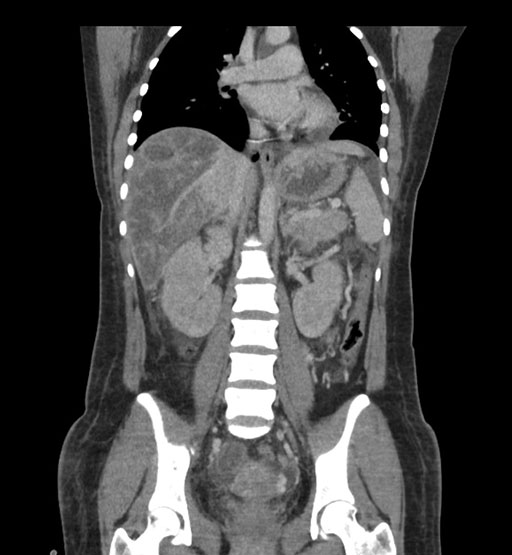

Coronal Venous

Imaging analysis

Based on initial findings, which issue(s) would you be most concerned about?